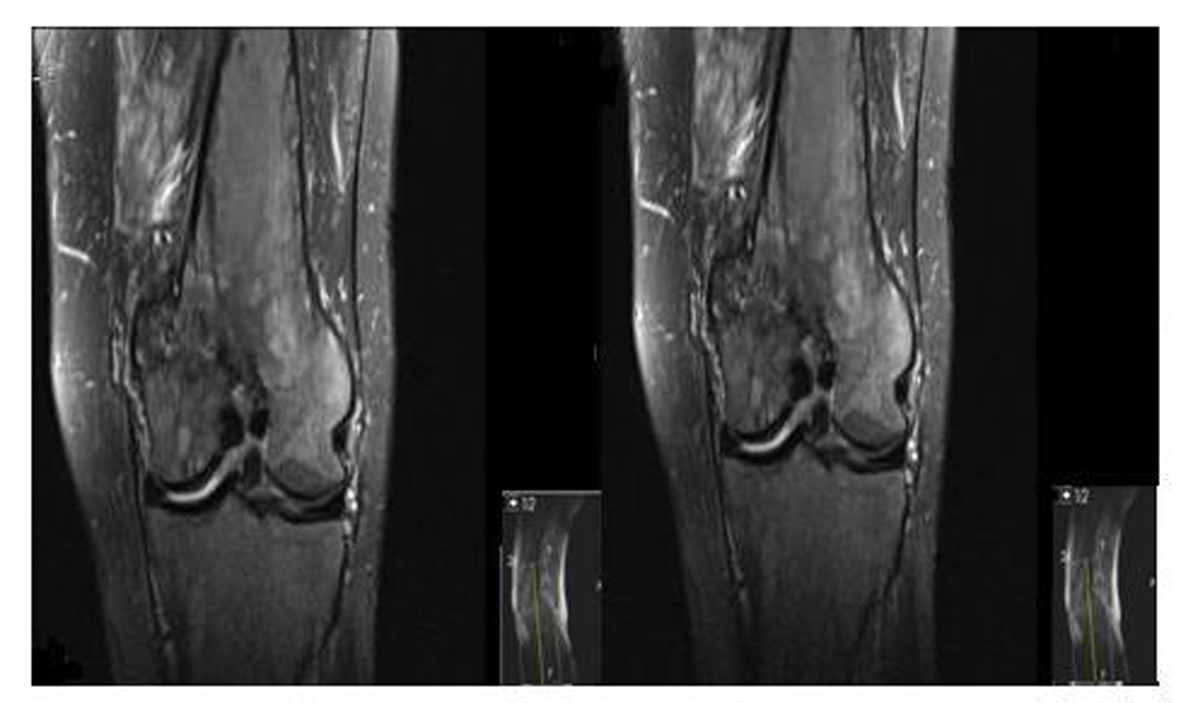

A 62-year-old male patient with knee pain, fatigue, night sweats and was admitted to our clinic. In patient history, central diabetes insipidus was diagnosed 3 months ago by nephrology clinic and vasopressin treatment was started. In laboratory examination, leukocyte counts 8.600/µL, hemoglobin level 12.6 g/dL, mean corpuscular volume 75 fL, platelet count 466.000/µL, blood urea nitrogen 8 mg/dL, creatinine 0.7 mg/dL, total protein 6.2 g/dL, albumin 2.8 g/dL, lactate dehydrogenase 184 U/L, sodium: 142 mmol/L, potassium 4.3 mmol/L, sedimentation 31 mm/h, C-reactive protein 6.17 mg/dL, thyroid stimulating hormone 2.1 µIU/mL. Peripheral blood revealed 65% neutrophils, 30% lymphocytes, 5% monocytes, cluster-platelet aggregates and normal red blood cell morphology. Immunoglobulin levels and immune fixation electrophoresis test were normal. Tomography of the abdomen and thorax was normal. Bone marrow examination was normocellular and no neoplastic infiltration. Jac-2, BCR-ABL were negative and karyotype was normal. Lytic lesions were detected in lower extremity radiographs (Fig. 1). Imaging signal changes were detected in bilateral distal part of the femur and proximal of tibia with by magnetic resonance (Fig. 2). Increased osteoblastic activity was detected in bilateral proximal and distal tibia by whole-body bone scintigraphy (Fig. 3). Biopsies were taken from tibia and was reported Langerhans cell histiocytosis (CD 1a (+), CD68 (+), Langerin (+), S-100 fokal (+)). Vinblastine 6 mg/m2 (6 weeks, 1 time per week), prednisolone 40 mg/m2/day (every day for 4 weeks) therapy was started. Zoledronic acid 4 mg/day treatment was started as once a month. After vinblastine, prednisolone therapy, patient was evaluated for response and progression was detected. Cladribine 0.14 mg/kg/day (for 5 days, 28 days) treatment was designed for 6 cure, 6 cure cladribine treatment was completed and patient was evaluated with knee MRI and whole-body bone scintigraphy again. These imaging techniques performed continuous regression.

![]() Click for large image | Figure 2. Pathological signal changes observed in both of knee joint. |

Bone involvement identifies in the most of patients with LCH. The patient may complain of pain in a localized area of bone and a raised, soft, tender spot are detected in examination. Radiologic studies typically demonstrate a lytic, “punched out” appearance. Soft tissue mass sometimes accompanies to lytic lesion. In a study, jaw (30 percent), skull (21 percent), vertebra (13 percent), pelvis (13 percent), extremity (17 percent), and rib (6 percent) were primary sites of bone involvement in adults [1]. Our patient admitted our clinic with knee pain. Lytic lesions were detected in lower extremity radiographs. Imaging signal changes were detected in bilateral distal part of the femur and proximal of tibia with by magnetic resonance and whole-body bone scintigraphy revealed increased osteoblastic activity in bilateral proximal and distal tibia. We thought multiple myelom as differential diagnosis, but immunoglobulin levels, immune fixation electrophoresis test were normal and there was no increased plasma cell in bone marrow examination.

Disease response is categorized to four groups; No evidence of active disease, complete resolution of all signs and symptoms, continuous regression; signs and/or symptoms are less prominent with no new lesions, Stable disease; persistence of signs and/or symptoms, Progressive disease; progression of signs/symptoms and/or appearance of new signs/symptoms [10]. After 6 weeks of vinblastine plus prednisolone treatment, knee MRI was applied and progression was seen in our patient.

There is a little information regarding the treatment of refractory LCH. For patients with low risk LCH who relapse less than 12 months from the end of the original vinblastine plus prednisolone treatment, single agent Cladribine (for six months therapy) results in responses in approximately 60 percent [11]. Our patient was applied 6 cure cladribine treatment. Knee MRI, whole-body bone scintigraphy were applied to patient again for response evaluation and continuous regression was detected after 6 cure cladribine therapy.